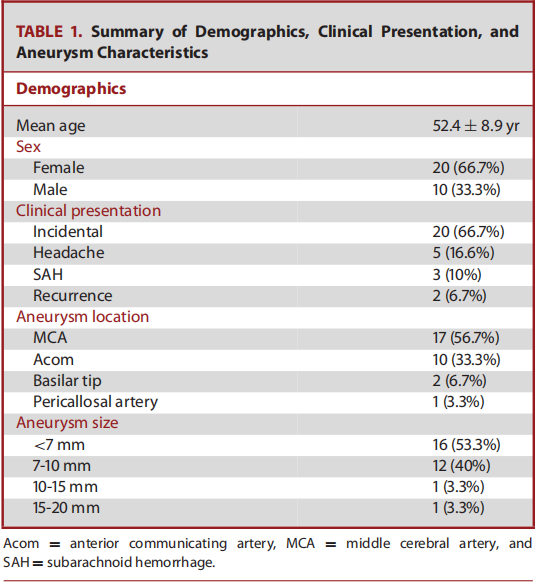

使用Neuroform Atlas支架用于Y型支架辅助栓塞技术,来治疗复杂性分叉动脉瘤。宽颈动脉瘤是指瘤体最大直径与瘤颈的比<2或颈径>4mm的动脉瘤。复杂的分叉动脉瘤定义为累及至少两个分支的宽颈分叉动脉瘤。在手术过程中,微导管超选时,首先在微导管到位困难的侧支血管内置入Excelsior SL-10(Stryker)微导管,然后另一个内径为0.0165英寸的微导管(Excelsior SL-10 or Headway 17; MicroVention/Terumo, Tustin, California)置入动脉瘤瘤体内。将第一个Neuroform Atlas支架释放到微导管到位存在困难的侧支血管内。随后以第一个Neuroform Atlas支架作为支撑,将同一Excelsior导管输送至第二分支,置入第二枚Atlas支架,与第一枚支架形成Y型支架。随后对动脉瘤进行致密栓塞。分别在术后即刻、术后3-6个月和9-15个月时进行DSA随访,采用Raymond–Roy (RR) 分级和载瘤动脉的畅通性来评估动脉瘤栓塞效果。采用改良的Rankin量表(mRS)对患者术前、术后即刻、出院、术后3-6个月和9-15个月的神经系统状况进行评估。记录患者术后出现的全部不良临床症状或体征,及围手术期和延迟并发症情况。

本研究回顾性分析了30例动脉瘤患者(20名女性)(表1)。纳入研究患者的平均年龄为52.4±8.9岁(34-66岁)。动脉瘤的瘤体最大直径为6.9±2.2 mm(4-16 mm)(图1)。分叉侧支的平均直径为2.2±0.3 mm(范围1.6-2.9 mm)。在支架展开或动脉瘤填塞的过程中,无操作相关并发症。术后即刻造影显示RR分级1级,2级,3级的患者例数分别为25例(83.3%),4例(13.3%),1例(3.3%)。无患者死亡,术后即刻神经系统检查较术前无变化。DSA造影随访平均时间为11.8±7.8月(6-36 月)。2名患者(6.7%)发生了围手术期(3.3%)或延迟并发症(3.3%)。上述延迟并发症导致患者永久性致残(3.3%)。全部患者的最终随访DSA结果显示:28例患者达到RR 1级闭塞(93.3%),2例患者实现RR 2级闭塞(6.7%)(表2)。在30例患者中,有28例患者临床随访显示mRS评分为0分。发生延迟性缺血性并发症的患者最终mRS评分为4分。一名术前mRS评分为2的患者术后随访mRS评分没有任何变化。